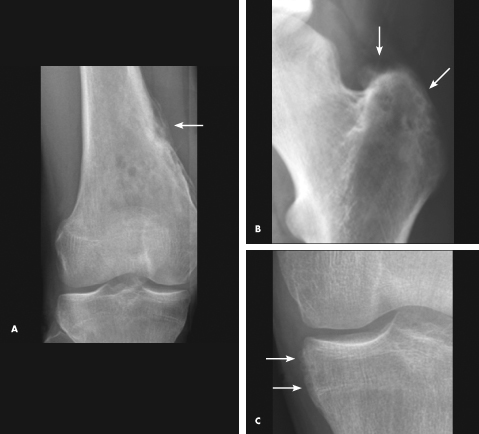

Nancy Pan, MD; Robert Schneider, MD; Austin Fragomen, MD; Kyriakos A. Kirou, MD

An 18-year-old boy with a long history of subjective fevers associated with recurrent right knee pain and swelling presented to our institution for a second opinion.

osteochondritis

William Yaakob, MD; Roli Agrawal, MD; Sarah Kizilbash, MD

<P><IMG style="MARGIN: 5px; FLOAT: left" src="/sites/default/files/transfer/1203CFP_RQAgrawal_IndexFg_thumb.jpg" width=90 height=70><BR>A 14-year-old boy presents to...